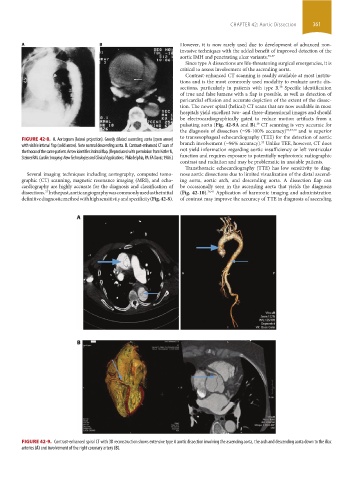

FIGURE 42-8. A. Aortogram (lateral projection). Grossly dilated ascending aorta (open arrow) to transesophageal echocardiography (TEE) for the detection of aortic

with visible intimal flap (solid arrow). Note normal descending aorta. B. Contrast-enhanced CT scan of branch involvement (̴96% accuracy). Unlike TEE, however, CT does

the thorax of the same patient. Arrow identifies intimal flap. (Reproduced with permission from Kotler N, not yield information regarding aortic insufficiency or left ventricular

Steiner RM. Cardiac Imaging: New Technologies and Clinical Applications. Philadelphia, PA: FA Davis; 1986.) function and requires exposure to potentially nephrotoxic radiographic

Several imaging techniques including aortography, computed tomo- nose aortic dissections due to limited visualization of the distal ascend-

graphic (CT) scanning, magnetic resonance imaging (MRI), and echo- ing aorta, aortic arch, and descending aorta. A dissection flap can

cardiography are highly accurate for the diagnosis and classification of be occasionally seen in the ascending aorta that yields the diagnosis

dissections. In the past, aortic angiography was commonly used as the initial (Fig. 42-10). 36,41 Application of harmonic imaging and administration

definitive diagnostic method with high sensitivity and specificity (Fig. 42-8). of contrast may improve the accuracy of TTE in diagnosis of ascending

FIGURE 42-9. Contrast-enhanced spiral CT with 3D reconstruction shows extensive type A aortic dissection involving the ascending aorta, the arch and descending aorta down to the iliac

arteries (A) and involvement of the right coronary artery (B).